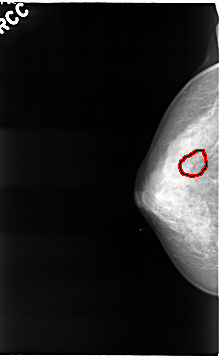

C_0036_1.RIGHT_MLO

RIGHT_CC LINES 4672 PIXELS_PER_LINE 2848 BITS_PER_PIXEL 12 RESOLUTION 50 OVERLAY

FILE: C_0036_1.RIGHT_CC.OVERLAY

TOTAL_ABNORMALITIES 1

ABNORMALITY 1

LESION_TYPE CALCIFICATION TYPE PUNCTATE DISTRIBUTION CLUSTERED

ASSESSMENT 4

SUBTLETY 4

PATHOLOGY MALIGNANT

TOTAL_OUTLINES 1

BOUNDARY